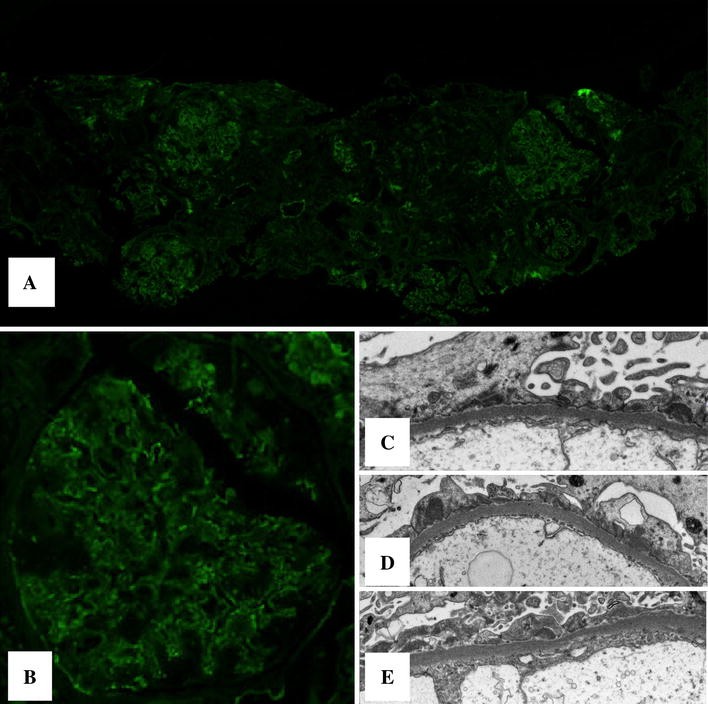

Renal biopsy before treatment for immunofluorescence and electron microscopy. a Immunofluorescence with anti-IgG (FITC-anti-human) showed weak capillary staining (extracted from whole slide image). b Magnification of a representative affected glomerulus (FITC-anti-human; extracted from whole slide image). c–e Electron microscopy revealed diffuse foot process effacement and sparse subepithelial deposits